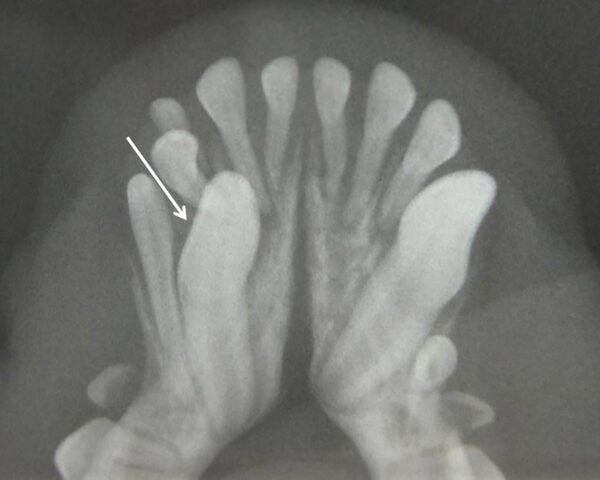

Aumento del número de dientes

La presencia de dientes supernumerarios también debe ser estudiada mediante la radiología intraoral. La causa principal es genética y la radiología nos permitirá valorar su naturaleza, si se trata de un diente definitivo o la falta de exfoliación de dientes deciduos (en caso de no tenerlo claro a la inspección visual). En este último caso, podremos valorar el estado de la raíz y su relación con el diente permanente, aspectos que debemos tener en cuenta a la hora de realizar su extracción (imágenes 18 y 19).

Las consecuencias pueden ser insignificantes en zonas de mínima intercuspidación, pero pueden ser causa de lesiones traumáticas o apiñamiento que disminuyan los mecanismos fisiológicos de autolimpieza.